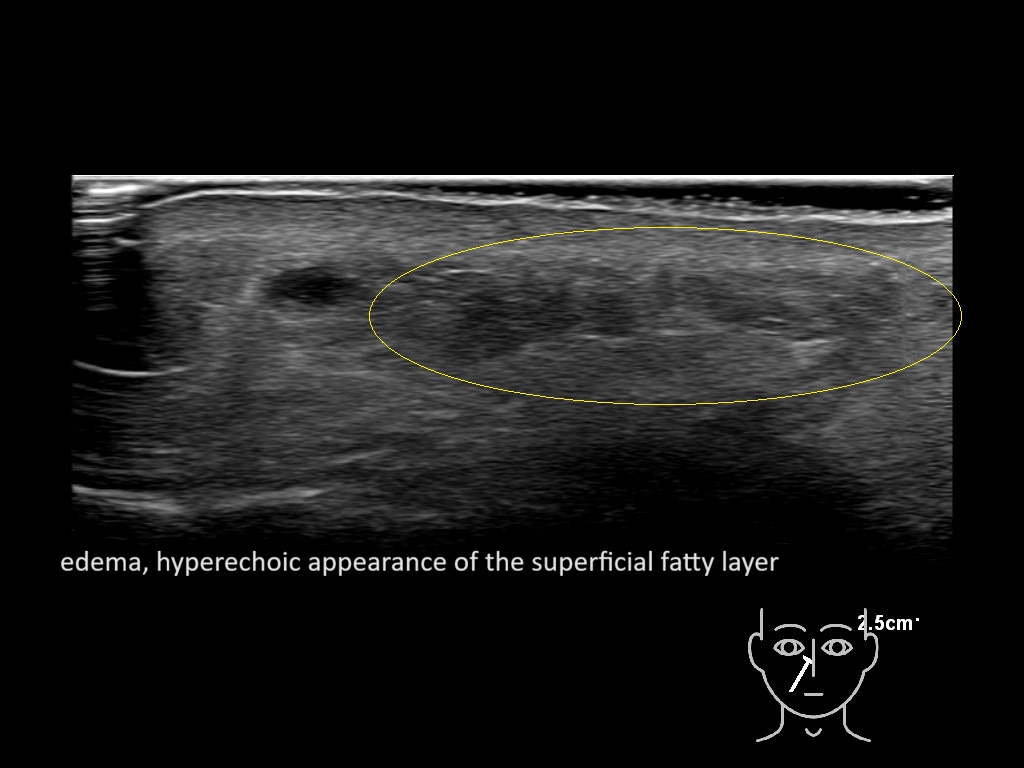

With ultrasound signs of inflammation can be visualized. Edema can be seen as a hyperechoic appearance of the subcutaneous fat, sometimes separated by hypoechoic fluid filled area’s, known as cobblestone appearance. Increased vascularization (hypervascularity) can be seen on colour Doppler. An abscess will appear as a fluid collection appearing as an irregular hypoechoic area with heterogeneous internal echoes and a thickened wall. Posterior acoustic enhancement can be present, and there is vascularity around but not within the mass. Under ultrasound guidance, abscesses can be managed by needle aspirations (18G) under antibiotic cover.

Study the first image to recognize the different layers. If you are sure about the layers, swipe to the second image to view the answer (if applicable).